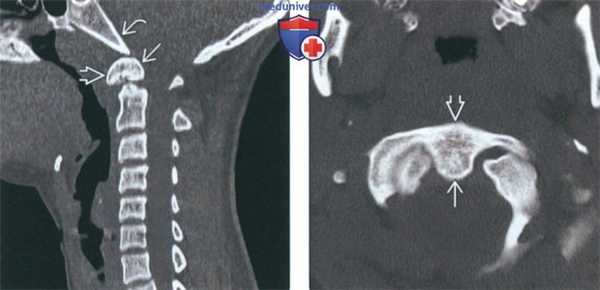

(Справа) Это сагиттальное Т2-ВИ получено в положении разгибания и отражает нормальное расположение зубовидной кости. В положении сгибания эта кость смещается кпереди, что свидетельствует об атлантоаксиальной нестабильности. (Слева) КТ шейного отдела позвоночника, сагиттальный срез: врожденное сращение передней дуги С1 и крупной зубовидной костив. Нормальные взаимоотношения между скатом В и зубовидной костью сохранены. Субаксиальные сегменты шейного отдела позвоночника во всех отношениях нормальны, признаков каких-либо других аномалий сегментации не выявлено.

(Справа) Аксиальный КТ-срез подтверждает наличие прочного врожденного сращения ортотопичной зубовидной кости с передней дугой С1. Задняя дуга С1 сформирована полностью (здесь не видно). (Слева) КТ, сагиттальный-срез: сращение крупной дистопичной зубовидной кости с передней дугой С1. Вершина ската с признаками минимального ремоделирования (уплощена). Укороченный и закругленный зубовидный отросток диспластичен.

(Слева) На сагиттальной КТ шейного отдела позвоночника в костном окне определяется врожденное слияние передней дуги С1 и крупной зубовидной кости. Соотношение зубовидной кости со скатом не нарушено. Шейный отдел позвоночника ниже осевого позвонка в остальном не изменен, нарушения сегментации других позвонков не выявлены.

(Справа) На аксиальной КТ в костном окне определяется врожденное слияние орто-топической зубовидной кости с передней дугой С1 по средней линии. Задняя дуга С1 не имеет дефектов (на этом срезе не видна).в) Дифференциальная диагностика зубовидной кости: